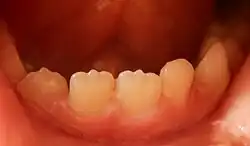

A mamelon (from French mamelon, "nipple") is one of three rounded protuberances which are present on the cutting edge of an incisor tooth when it first erupts through the gum. Mamelons' appearance can be smoothed by a dentist if they have not been worn down naturally by biting and eating foods.[1] Mamelons are present on permanent central and lateral incisors. Mamelons are easiest to observe on the maxillary central incisors, and appear as three small prominences on the incisal edge of the tooth.[2] Mamelons are ordinarily of no clinical importance.[3] Usually, they are worn off early in the life of the tooth.